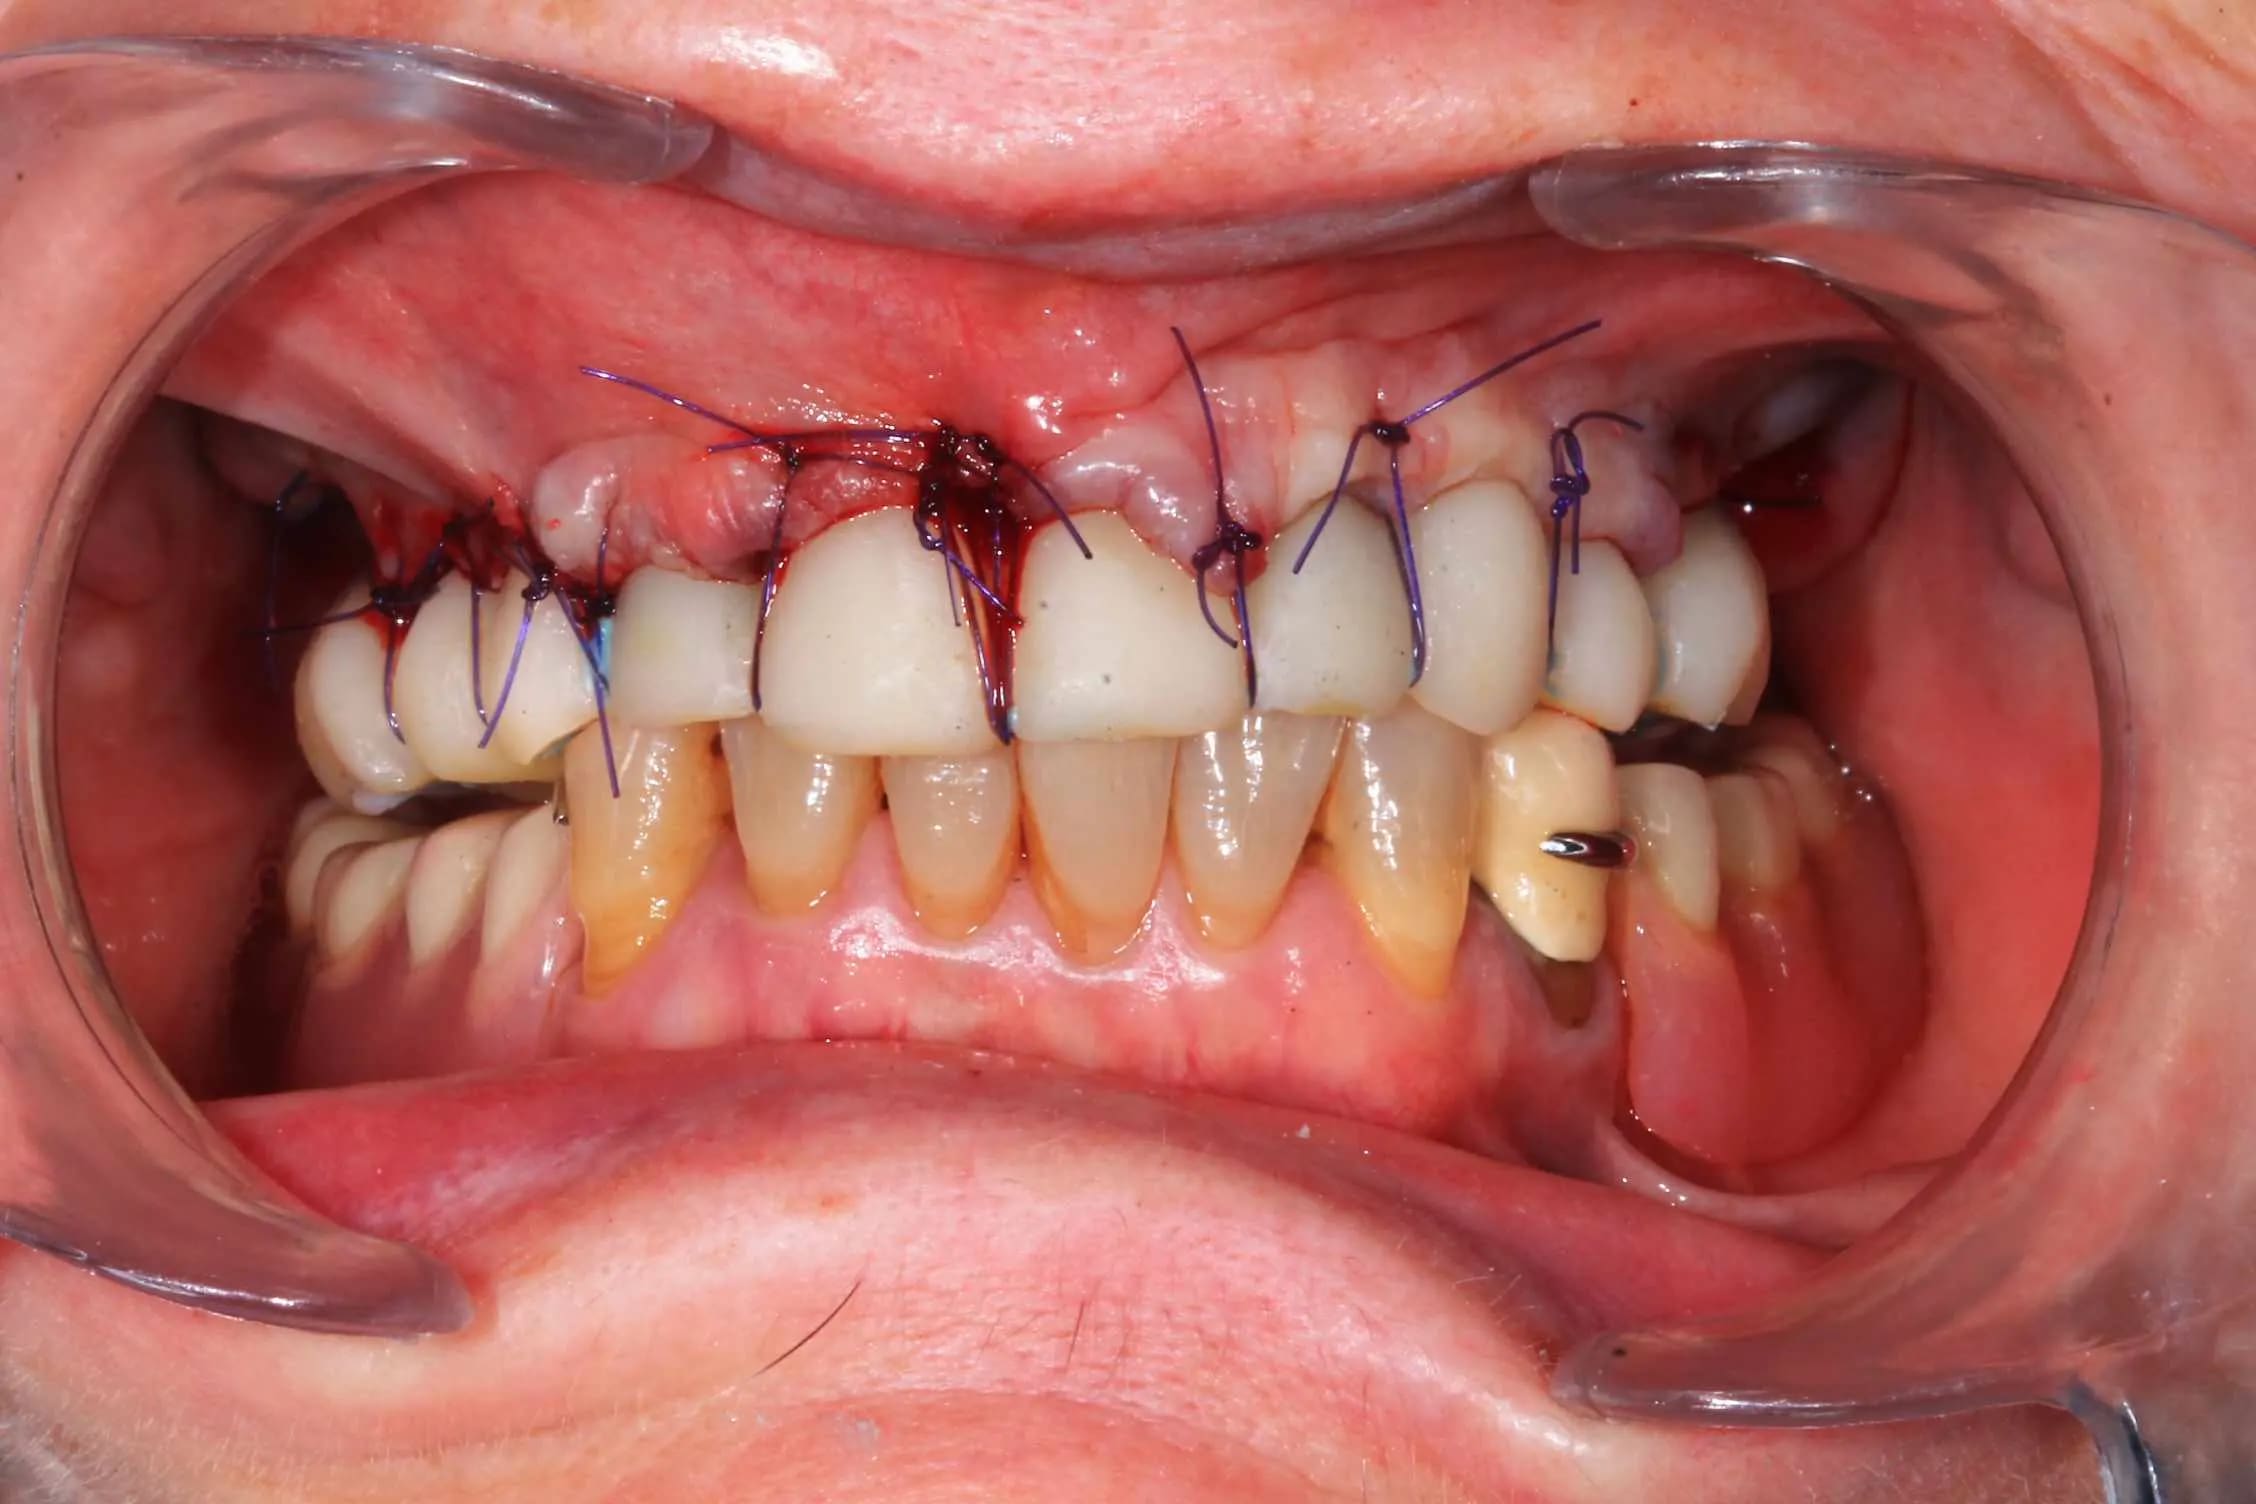

Guide métal avec support clavette, os assez fin : il est prévu un sticky bone complet : donc : lambeau avant extraction, positionnement du guide base et forage des clavettes, positionnement du guide implant, pose des piliers MU, controle des axes prothétique avec le guide pilier, collage des piliers prov sur le bridge a armature métal, occlusion nickel, sticky bone et PRF, sutures suspendues.

Ce qui ne vas pas : les dents un peu trop courte sur le provisoires, et le plan d'occlusion. L'erreur est de ne pas avoir utilisé Cadsmile3d pour le smile design du provisoire.

Ce n'est pas grand chose a prendre en compte pour le definitif.

Et surtout : j'ai creer une bonne courbe d'occlusion ideal, mais je n'ai pas imprimé de piste a coller sur son vieux stellite. Je vais rajouter de la résine samedi.